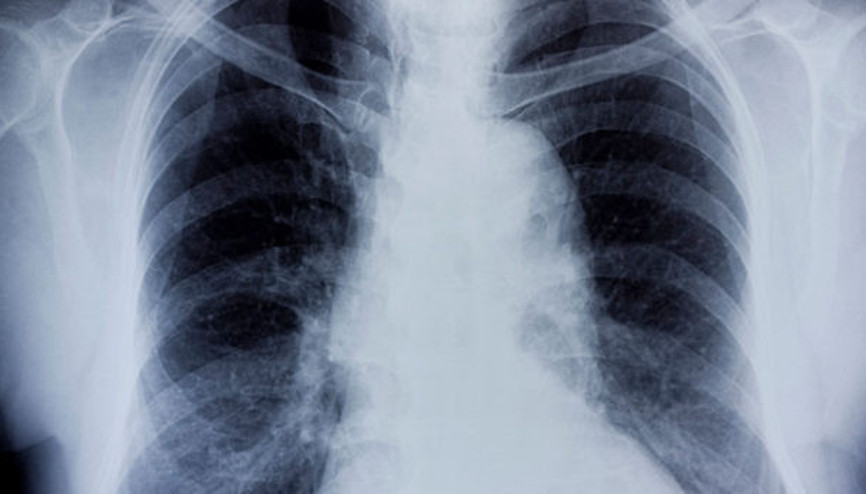

#Charlotte DawsonBronşit, her yaştan kişiyi etkileyen bir solunum sistemi rahatsızlığı. Grip ve nezle gibi soğuk algınlığına neden olan virüsler bronşite neden olabilir. Peki bronşit nedir, neden olur? İşte bronşit belirtileri ve tedavisi hakkında bilgiler...

#ÇocukKış mevsiminin kendini hissettirmesi ile birlikte çocuklarda çok sık meydana gelen bronşit, yetişkinlerin de başına gelebilmektedir. Akut ve kronik olarak iki farklı tipte bronşitin meydana gelmesi kişide; geçici olabilirken başka başka hastalıklara da yol açmaktadır. Kronik olma olasılığı olan bronşit için mutlaka doktora danışmanız gereklidir. Bronşit belirtileri, bronşit nasıl geçer, bronşite ne iyi gelir ve bronşit neden olur sorularının yanıtlarını sizler için bir araya getirdik.

#Bronşit Nasıl Geçer Ve Ne İyi Gelir?Kışın en sık karşılaşılan hastalıklarından biri bronşittir. Bronşit nedir? Bronşit neden olur? Bronşit belirtileri nelerdir ve nasıl tedavi edilir?Göğüs Hastalıkları Uzmanı Dr. Kanan Abbaslı, bronşit ile ilgili bilinmesi gerekenleri anlatıyor.

#Bronşite Kökten ÇözümBir solunum sistemi sorunu olan bronşit, zaman zaman kişilerin hayatını zorlaştırabiliyor. Bronşit hastalığından muzdarip olan kişiler, nefes darlığı, öksürük ve hırıltılı solunum gibi şikayetler yaşar. Bu nedenle kirli havadan korunması ve bol su tüketmesi önerilir. Peki, bronşit tam olarak nedir?

#Bronşit NedirBronşit nedir sorusunun yanıtı birçok kişi tarafından sorgulanan ve merak edilen konular arasında yer almaya başladı. Havaların soğumasıyla birlikte vatandaşlar sık sık rahatsızlanmamak adına önlem almaya başladı. Soğuk hava rahatsızlığı olarak da görülen bronşitin en belirgin özelliği öksürüktür. Peki, bronşit nedir? İşte bronşit çeşitleri.